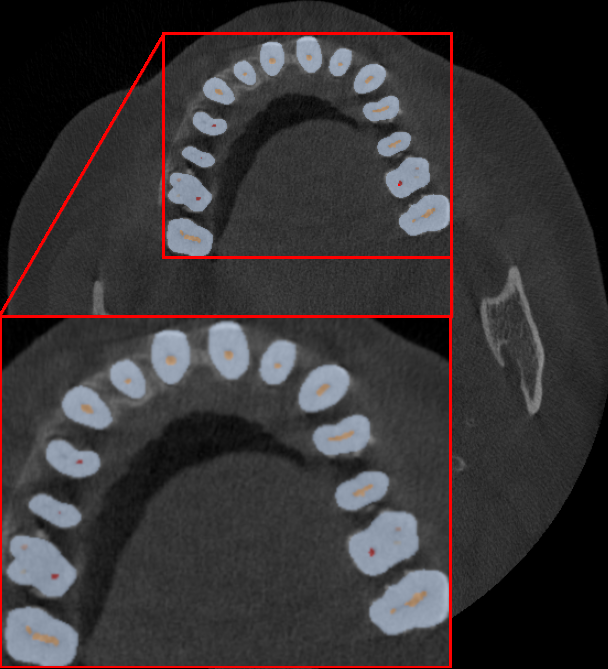

4.2 Qualitative Results

Fig.˜2 shows the qualitative comparison between the ground truth and our model’s predictions of the scans with the highest and lowest DSC in our internal validation set, in the top and bottom rows, respectively. Generally, we observe that our method can accurately differentiate between the tooth and different classes of pulp and root canal. The failure cases of our method typically stem from the inability to precisely predict the thickness and the length or extent of the pulp. Moreover, our model also struggles with limited field of view (LFOV) CBCTs where it predicts more false positives around the image edges.